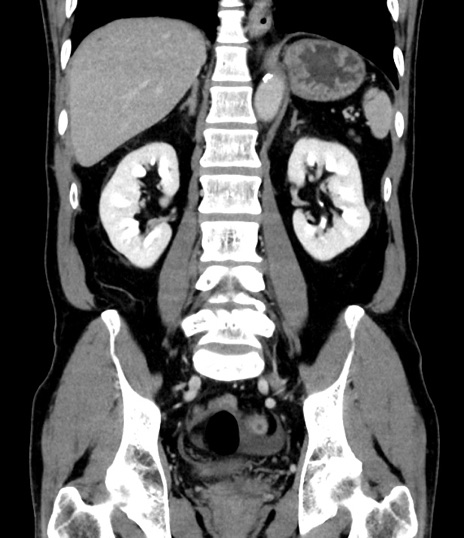

症例8(冠状断像)

【症例】 60歳代男性

【主訴】 黒色吐物

【現病歴】 4日前から嘔気自覚、2日前の朝食後にも嘔気あり、自分で手で嘔吐反射起こし嘔吐したところ血が混ざっていたため受診。

【既往歴】 5年前汎発性腹膜炎を伴う急性虫垂炎で手術、高血圧、前立腺肥大症、高脂血症

【身体所見】 腹部正中に手術癩痕あり 腹部平坦・軟圧痛なし膨満感あり

【データ】WBC 8400、CRP 4.54